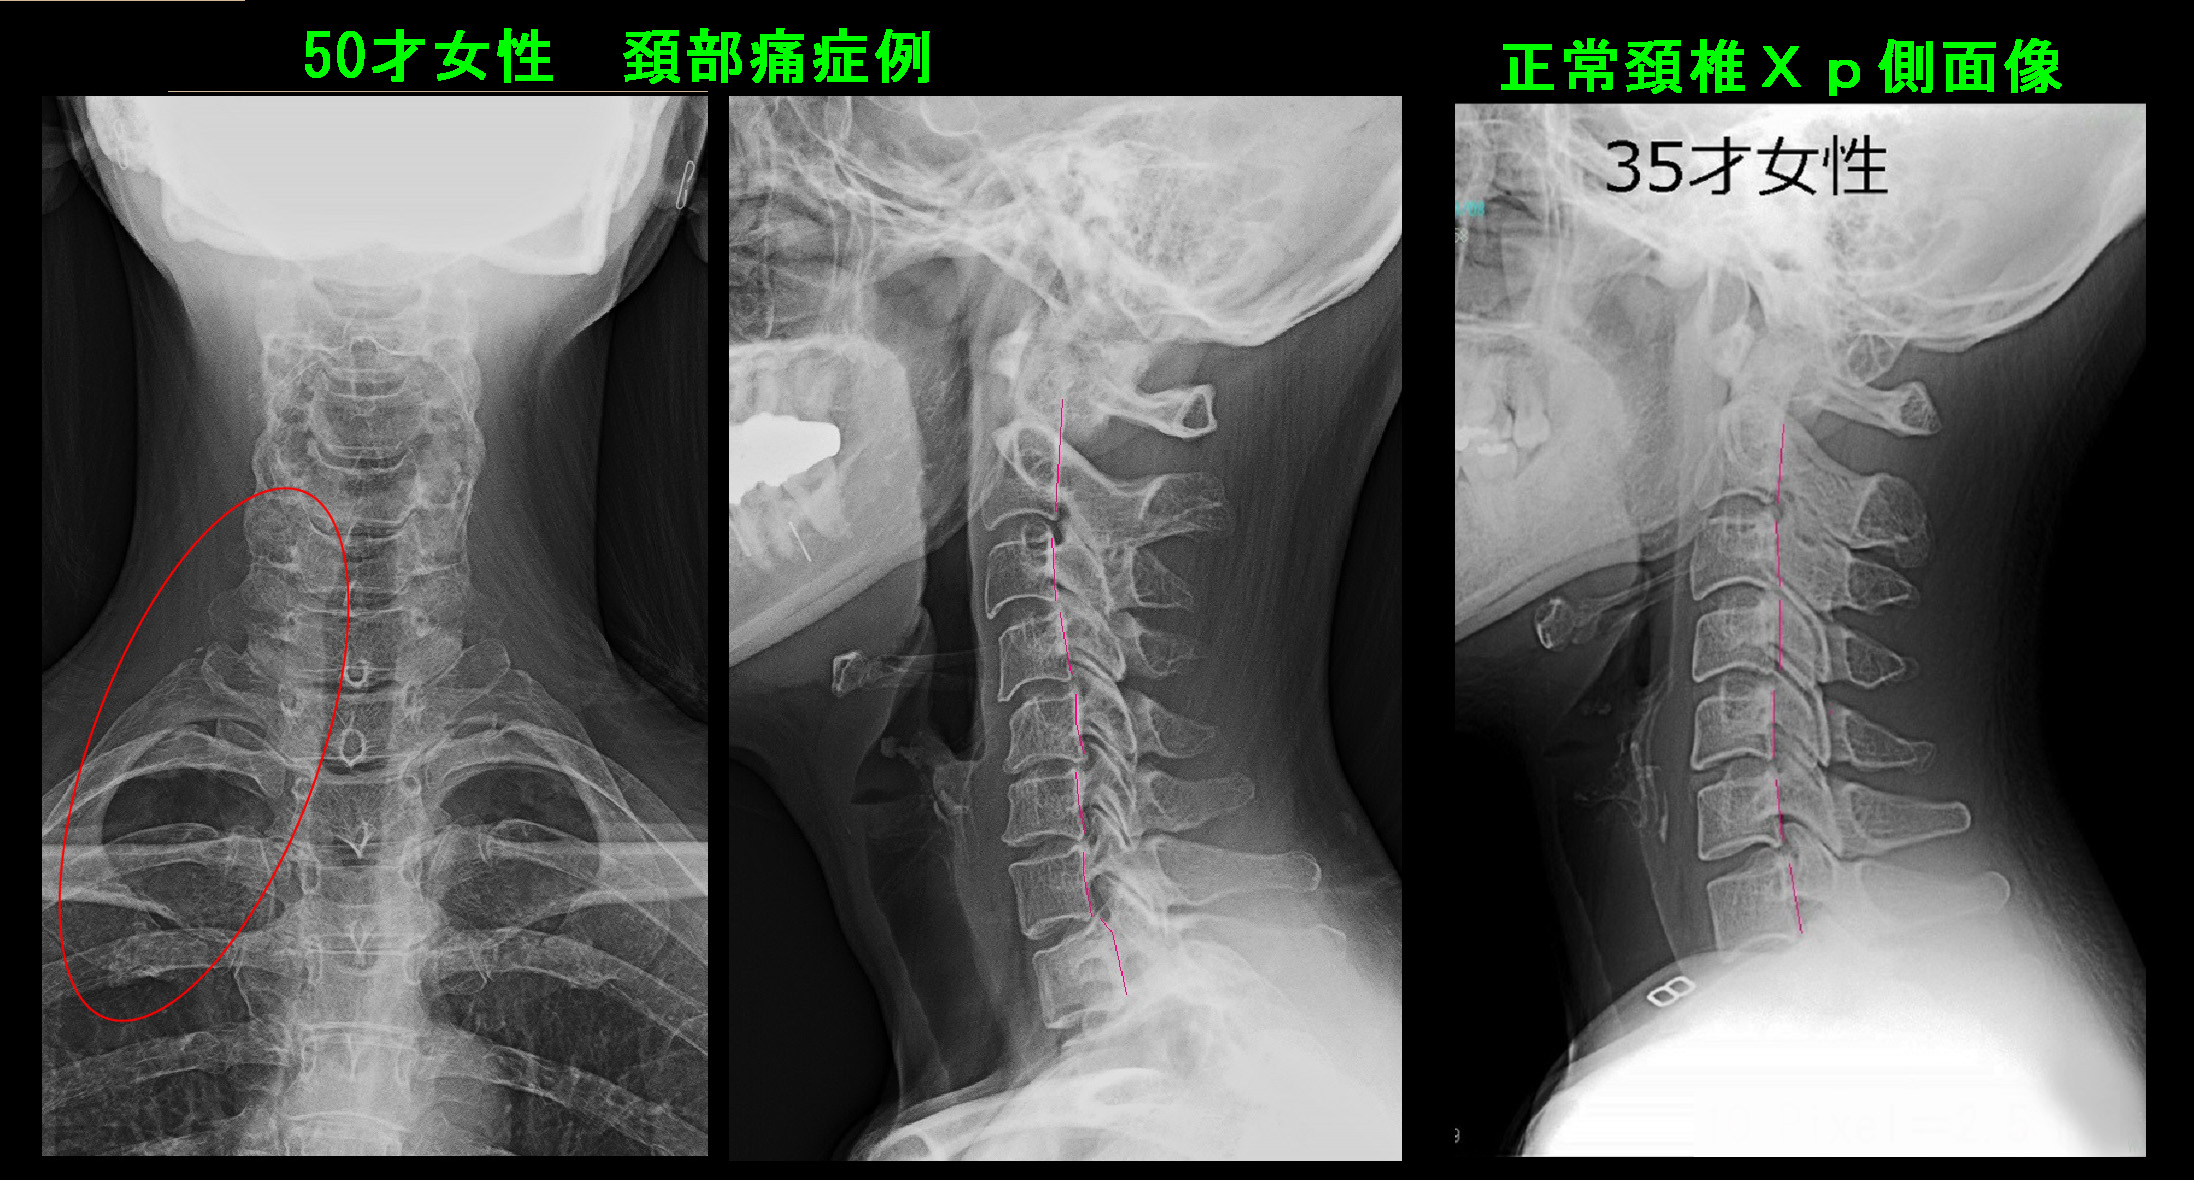

頚椎のレントゲン像では軽度の頚椎症(首の加齢性変化です)を認めます。

50才女 Xp1.jpg